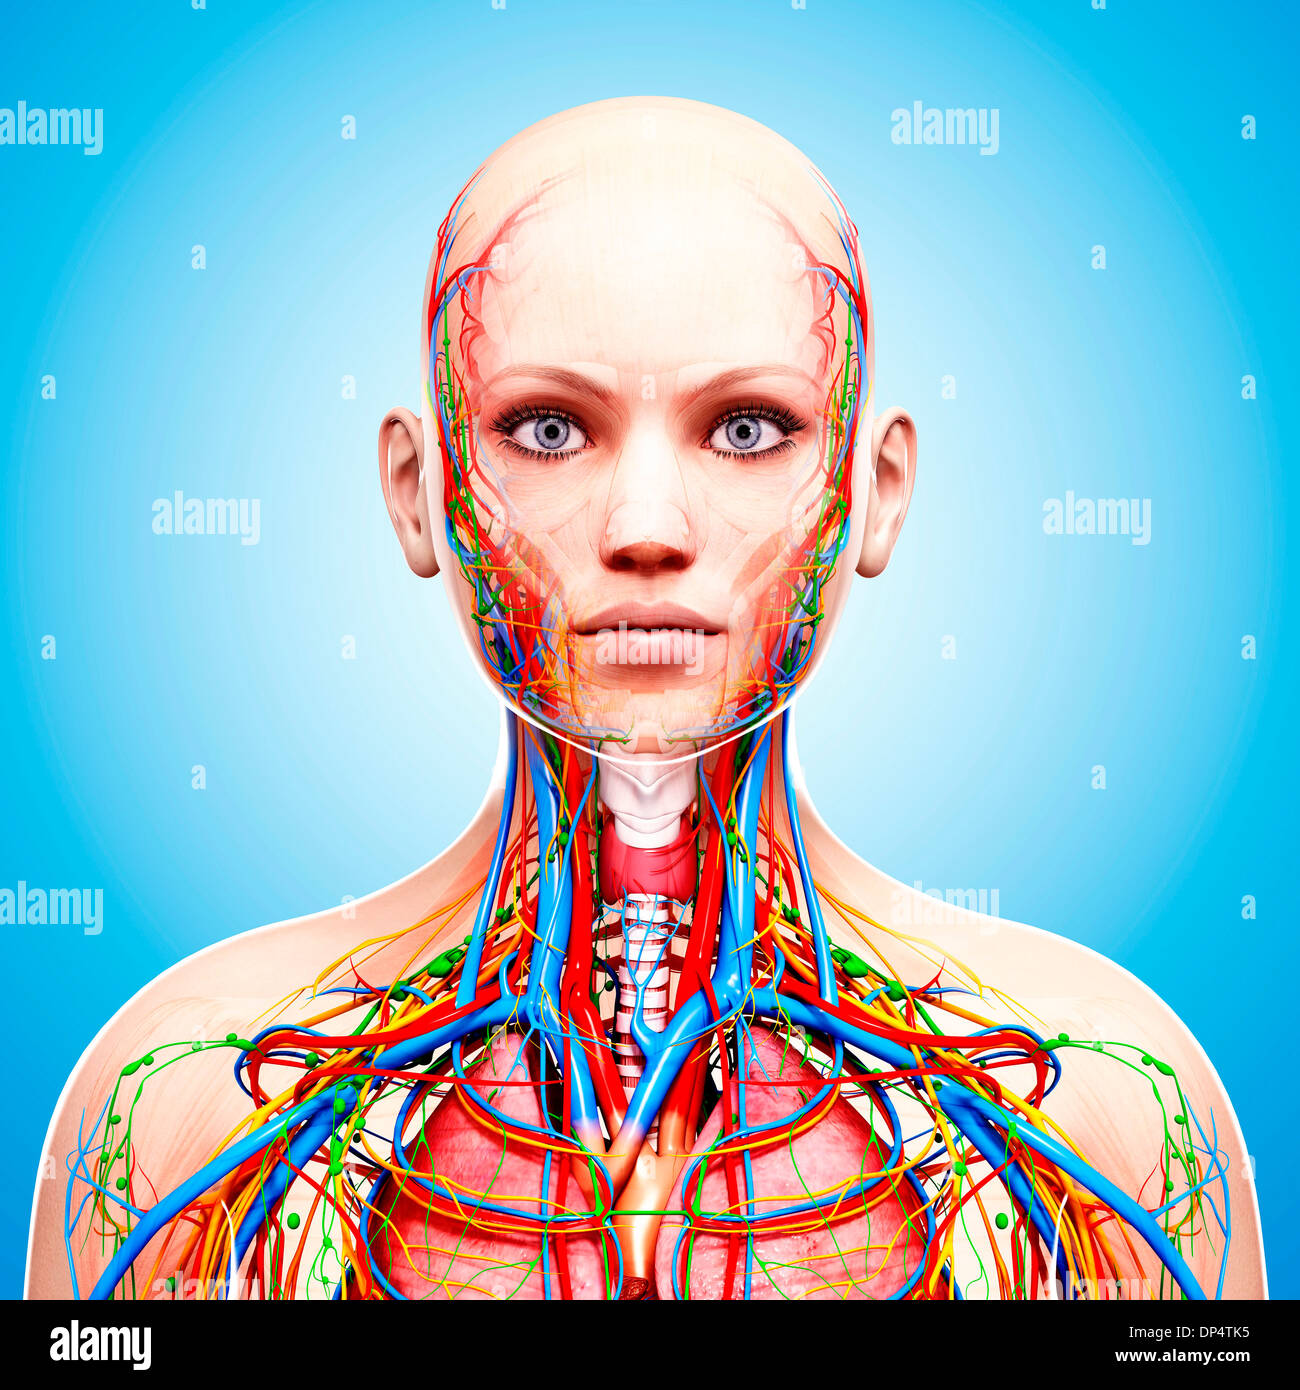

Female Anatomy Photograph By Pixologicstudio/science Photo Library

fineartamerica.comFemale Anatomy Photograph By Pixologicstudio/science Photo Library

fineartamerica.comFemale Anatomy Photograph By Pixologicstudio/science Photo Library

www.alamy.comFemale Anatomy Photograph By Pixologicstudio/science Photo Library

www.alamy.comFemale Anatomy Photograph By Pixologicstudio/science Photo Library

www.alamy.comFemale Anatomy Photograph By Pixologicstudio/science Photo Library

www.alamy.comFemale Anatomy Photograph By Pixologicstudio/science Photo Library

www.alamy.comFemale Anatomy Photograph By Pixologicstudio/science Photo Library

www.alamy.comFemale Anatomy Photograph By Pixologicstudio/science Photo Library

Female Anatomy Photograph By Pixologicstudio/science Photo Library

www.alamy.comFemale Anatomy Photograph By Pixologicstudio/science Photo Library

www.alamy.comFemale Anatomy Photograph By Pixologicstudio/science Photo Library

www.alamy.comFemale Anatomy Photograph By Pixologicstudio/science Photo Library

www.alamy.comFemale Anatomy Photograph By Pixologicstudio/science Photo Library

fineartamerica.comanatomy pixologicstudio artwork 26th

fineartamerica.comanatomy pixologicstudio artwork 26th

www.alamy.comFemale Anatomy Photograph By Pixologicstudio/science Photo Library

www.alamy.comFemale Anatomy Photograph By Pixologicstudio/science Photo Library

www.alamy.comFemale Anatomy Photograph By Pixologicstudio/science Photo Library | Pixels

www.alamy.comFemale Anatomy Photograph By Pixologicstudio/science Photo Library | Pixels

www.alamy.comFemale anatomy art print women body torso drawing illustration modern. Female anatomy photograph by pixologicstudio/science photo library. Female anatomy, artwork stock photo

www.alamy.comFemale anatomy art print women body torso drawing illustration modern. Female anatomy photograph by pixologicstudio/science photo library. Female anatomy, artwork stock photo